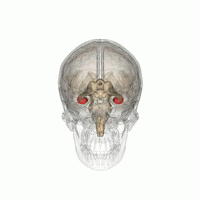

图片[编辑 | 编辑源代码]

- Hippocampus and seahorse cropped.JPG

大脑的海马区(左)和海马(右)。